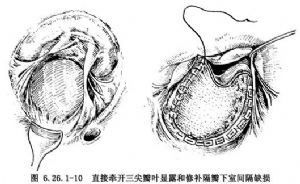

③隔瓣下缺損修補方法:隔瓣下缺損又稱房室管型室間隔缺損,該部位缺損常被三尖瓣隔瓣掩蓋。於三尖瓣隔瓣置2根牽引線,牽開三尖瓣隔瓣多可顯露其下方缺損。假如掩蓋室間隔缺損的瓣葉或腱索無法牽開,可於三尖瓣隔瓣根部距瓣環2~3mm處切開三尖瓣,並將切開瓣葉牽往前方,隔瓣下方缺損即得到良好顯露(圖6.26.1-8)。三尖瓣隔瓣直接與缺損相鄰,頭、尾側分別爲鬥隔和小梁隔,以及右室流入道間隔。頭側三尖瓣隔瓣裂常指向中央纖維體,三尖瓣下方室間隔缺損後下緣有傳導束經過,穿越中央纖維體後分爲左右束支,左束支在室間隔左室面內膜下行走,右束支在室間隔膜部下方分出後,於右室面心內膜下向前進入調節束抵達前乳頭肌基部。圖6.26.1-8插圖顯示了冠狀靜脈竇、房室結,房室束和束支走行與室間隔缺損關係。應用帶墊片和褥式縫線於缺損後下緣做5~6間斷褥式縫合,鄰近三尖瓣環處的縫線縫於三尖隔瓣根部,其他部位縫線緣縫於室間隔的右室側,以免損傷傳導束。上述縫線分別穿過補片相應邊緣並結紮(圖6.26.1-9A)。然後以5-0無創縫線縫合切開的三尖瓣(圖6.26.1-9B)。然而大多數情況下閉合此類缺損可不需切開三尖瓣葉,僅需牽開三尖瓣隔瓣,顯露和修補隔瓣下缺損(圖6.26.1-10)。